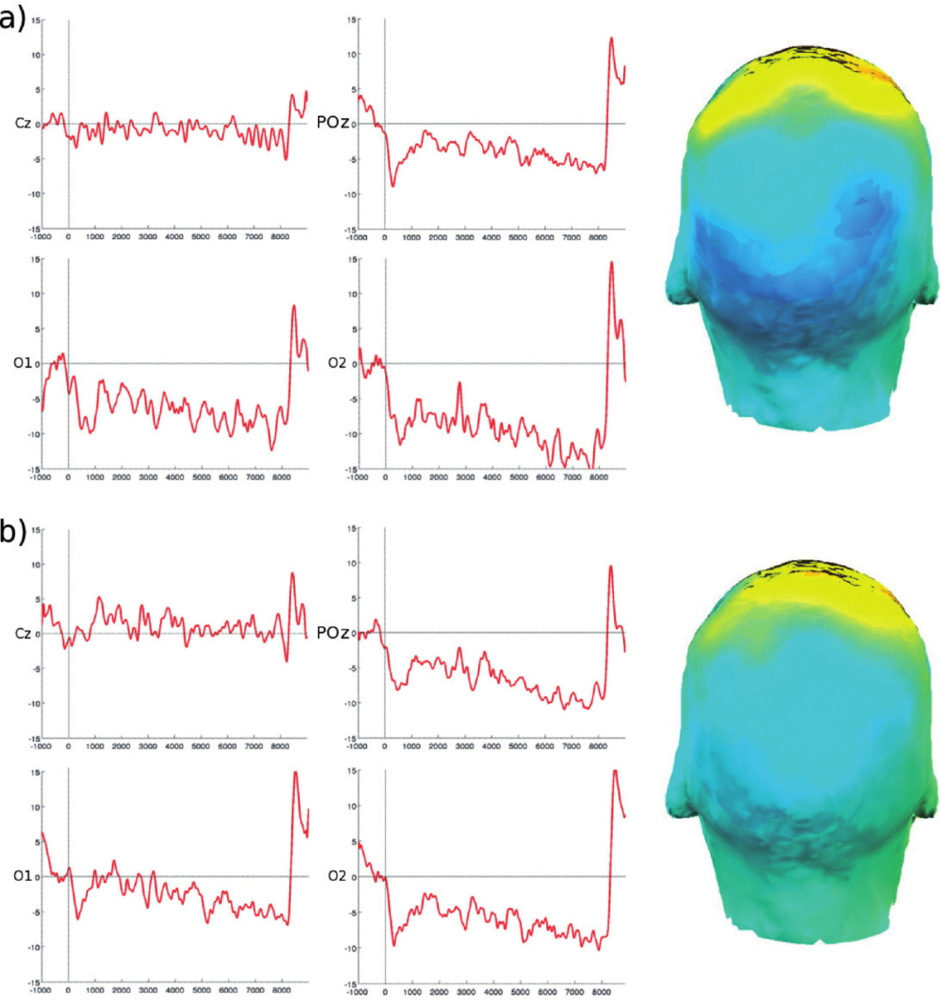

2.3. Multi-Modal Integration of MRI, fMRI, and Slow Cortical Potentials (SCP, DC-EEG)

Functional brain imaging: